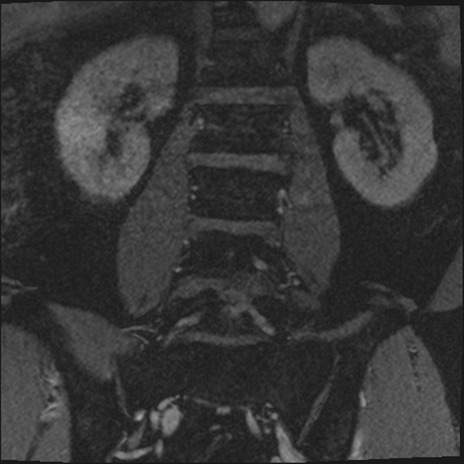

【整形】TIPS症例2 腰椎MRI 3D(冠状断像)

【症例】70歳代男性

【主訴】左下肢痛

【現病歴】2週間前くらいから腰痛、左下肢痛あり。左臀部から大腿、下腿外側のしびれが常時ある。歩行とともに同部位の痛みあり。

【身体所見】Lasegue70-/60+、Bragard-/±、PTR ±/±、ATR -/-、IP 5/5、TA 5/4、TS 5/5、EHL 右第1足趾なし/3、FHL 5/5、hypersthesia(-)、足背動脈触知良好

異常所見と診断は?